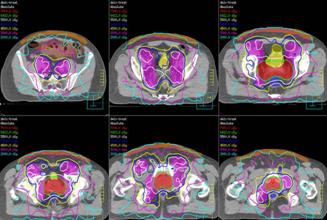

This type of capability is used to better target the area of cancer by the radiation beams enter from multiple angles. This helps to reduce the chance of injury to nearby body structures.

Photo: A radiation treatment plan for prostate IMRT.

Intensity modulated radiation therapy is an advanced form of 3D conformal that allows doctors to customize the radiation dose. It uses multiple small radiation beams to irradiate the tumor. The radiation of each beam is divided and can be set to deliver different intensities to focus on the tumor to spare the surrounding healthy tissue as much as possible.